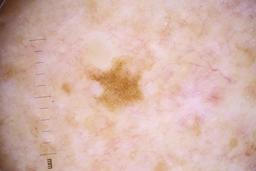

- Name: Challenge 2020: Training

- Number of images: 33,126

- Number of specified lesions: 32,701

- Number of specified patients: 2,056